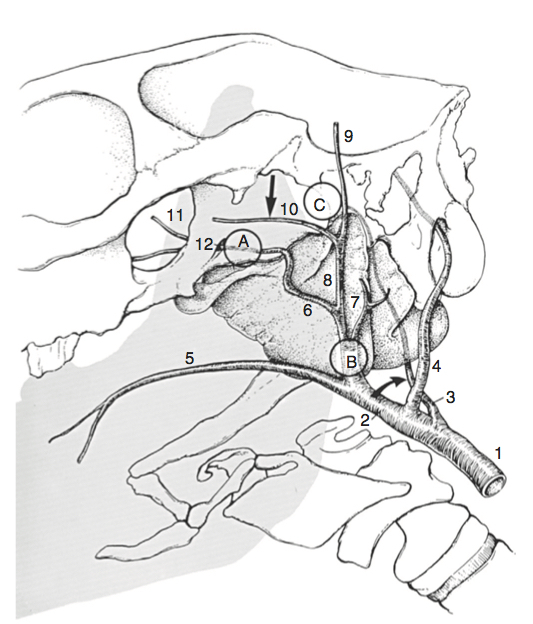

Describe the procedure for a prosthetic laryngoplasty

General anaesthesia Lateral recumbency, head and neck extended Videoendoscope secured transnasally Aseptic prep and drape 10-12cm skin incision ventral and parallel to linguofacial vein, extending caudally from point 4cm cranial to rams of mandible Blunt and sharp dissection with Metzenblum scissors separates linguofacial from lateral margin of omohyoideus along length of incision Elevation of lingufacial vein with Allis tissue forceps allows cleavage plane between sternocephalicus and cricothyroideus - digitally open and enlarge Exposes dorsal aspect of larynx 6-8cm wide malleable retractor placed under linguofacial vein and sternocephalicus muscle used to expose larynx Muscular process of arytenoid under cranial portion of cricopharyngeus and this is exposed by sharply separating the cricopharynxgeus and thyropharyngeus muscles along junction of aponeuroses (alternatively, plane of dissection created off black edge of cricopharynxgeus under vascular plexus that lies over CAD Avoid oesophagus, thyroid gland, laryngeal and thyroid vessels and ventral branch of first cervical and cranial laryngeal nerves Suture materials: braided polyester, with (No. 5 Micron) or without silicone coating, 6mm surgical stainless steel wire, braided lycra, nylon Needle: large swaged on reverse cutting needle or No. 3 Martin uterine reverse-cutting needle Two suture placed Suture placed through cricoid cartilage - walk needle off caudal edge of cricoid 2-3mm lateral to dorsal midline. Needle advanced cranially while avoiding penetration into lumen of larynx. Needle penetrates cricoid 2-3cm cranial to caudal border and 1cm lateral to dorsal ridge Check laryngeal lumen on scope Second suture placed and held with haemostats Suture placed through muscular process.Used No. 6 Mayo needle or No. 6 Martin uterine needle (3mm bone trochar can be used to make tunnel, or 12-16Ga hypodermic needle can make tunnel) Optional to transect tendon of intention of CAD and open cricoarytenoideus articulation and curette joint space (PMMA can also be used) prior to placement of suture Place needle through muscular process from caudomedial to craniolateral direction or caudal to cranial direction Place tension on sutures to remove slack. Tie sutures and visualise larynx. Leave cut ends of suture 1.5-2cm long. Need to achieve 88% of cross sectional rims glottis area Thyropharyngeus and cricopharynxgeus muscles apposed with simple continuous 2-0 absorbable store Apposition of fascia adjacent to linguofacial vein to omohyoideus muscle with simple interrupted or continuous sutures of 2-0 absorbable suture Skin closed with staples or 2-0 non absorbable monofilament suture Stent bandage Can then perform ventriculcordectomy

General anaesthesia

Lateral recumbency, head and neck extended

Videoendoscope secured transnasally

Aseptic prep and drape

10-12cm skin incision ventral and parallel to linguofacial vein, extending caudally from point 4cm cranial to rams of mandible

Blunt and sharp dissection with Metzenblum scissors separates linguofacial from lateral margin of omohyoideus along length of incision

Elevation of lingufacial vein with Allis tissue forceps allows cleavage plane between sternocephalicus and cricothyroideus - digitally open and enlarge

Exposes dorsal aspect of larynx

6-8cm wide malleable retractor placed under linguofacial vein and sternocephalicus muscle used to expose larynx

Muscular process of arytenoid under cranial portion of cricopharyngeus and this is exposed by sharply separating the cricopharynxgeus and thyropharyngeus muscles along junction of aponeuroses (alternatively, plane of dissection created off black edge of cricopharynxgeus under vascular plexus that lies over CAD

Avoid oesophagus, thyroid gland, laryngeal and thyroid vessels and ventral branch of first cervical and cranial laryngeal nerves

Suture materials: braided polyester, with (No. 5 Micron) or without silicone coating, 6mm surgical stainless steel wire, braided lycra, nylon

Needle: large swaged on reverse cutting needle or No. 3 Martin uterine reverse-cutting needle

Two suture placed

Suture placed through cricoid cartilage - walk needle off caudal edge of cricoid 2-3mm lateral to dorsal midline. Needle advanced cranially while avoiding penetration into lumen of larynx. Needle penetrates cricoid 2-3cm cranial to caudal border and 1cm lateral to dorsal ridge

Check laryngeal lumen on scope

Second suture placed and held with haemostats

Suture placed through muscular process.Used No. 6 Mayo needle or No. 6 Martin uterine needle (3mm bone trochar can be used to make tunnel, or 12-16Ga hypodermic needle can make tunnel)

Optional to transect tendon of intention of CAD and open cricoarytenoideus articulation and curette joint space (PMMA can also be used) prior to placement of suture

Place needle through muscular process from caudomedial to craniolateral direction or caudal to cranial direction

Place tension on sutures to remove slack. Tie sutures and visualise larynx. Leave cut ends of suture 1.5-2cm long. Need to achieve 88% of cross sectional rims glottis area

Thyropharyngeus and cricopharynxgeus muscles apposed with simple continuous 2-0 absorbable store

Apposition of fascia adjacent to linguofacial vein to omohyoideus muscle with simple interrupted or continuous sutures of 2-0 absorbable suture

Skin closed with staples or 2-0 non absorbable monofilament suture

Stent bandage

Can the perform ventriculcordectomy